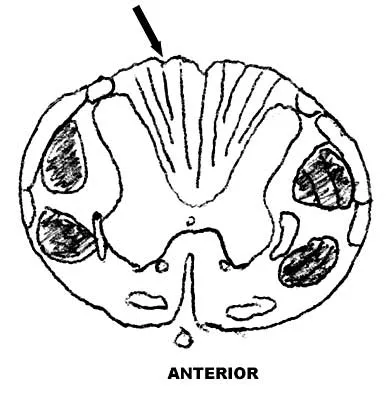

Figure 9 shows a cross-sectional view of the spinal cord at the lower cervical level. Injury to the structure indicated by the black arrow will lead to what neurologic deficit?

Explanation